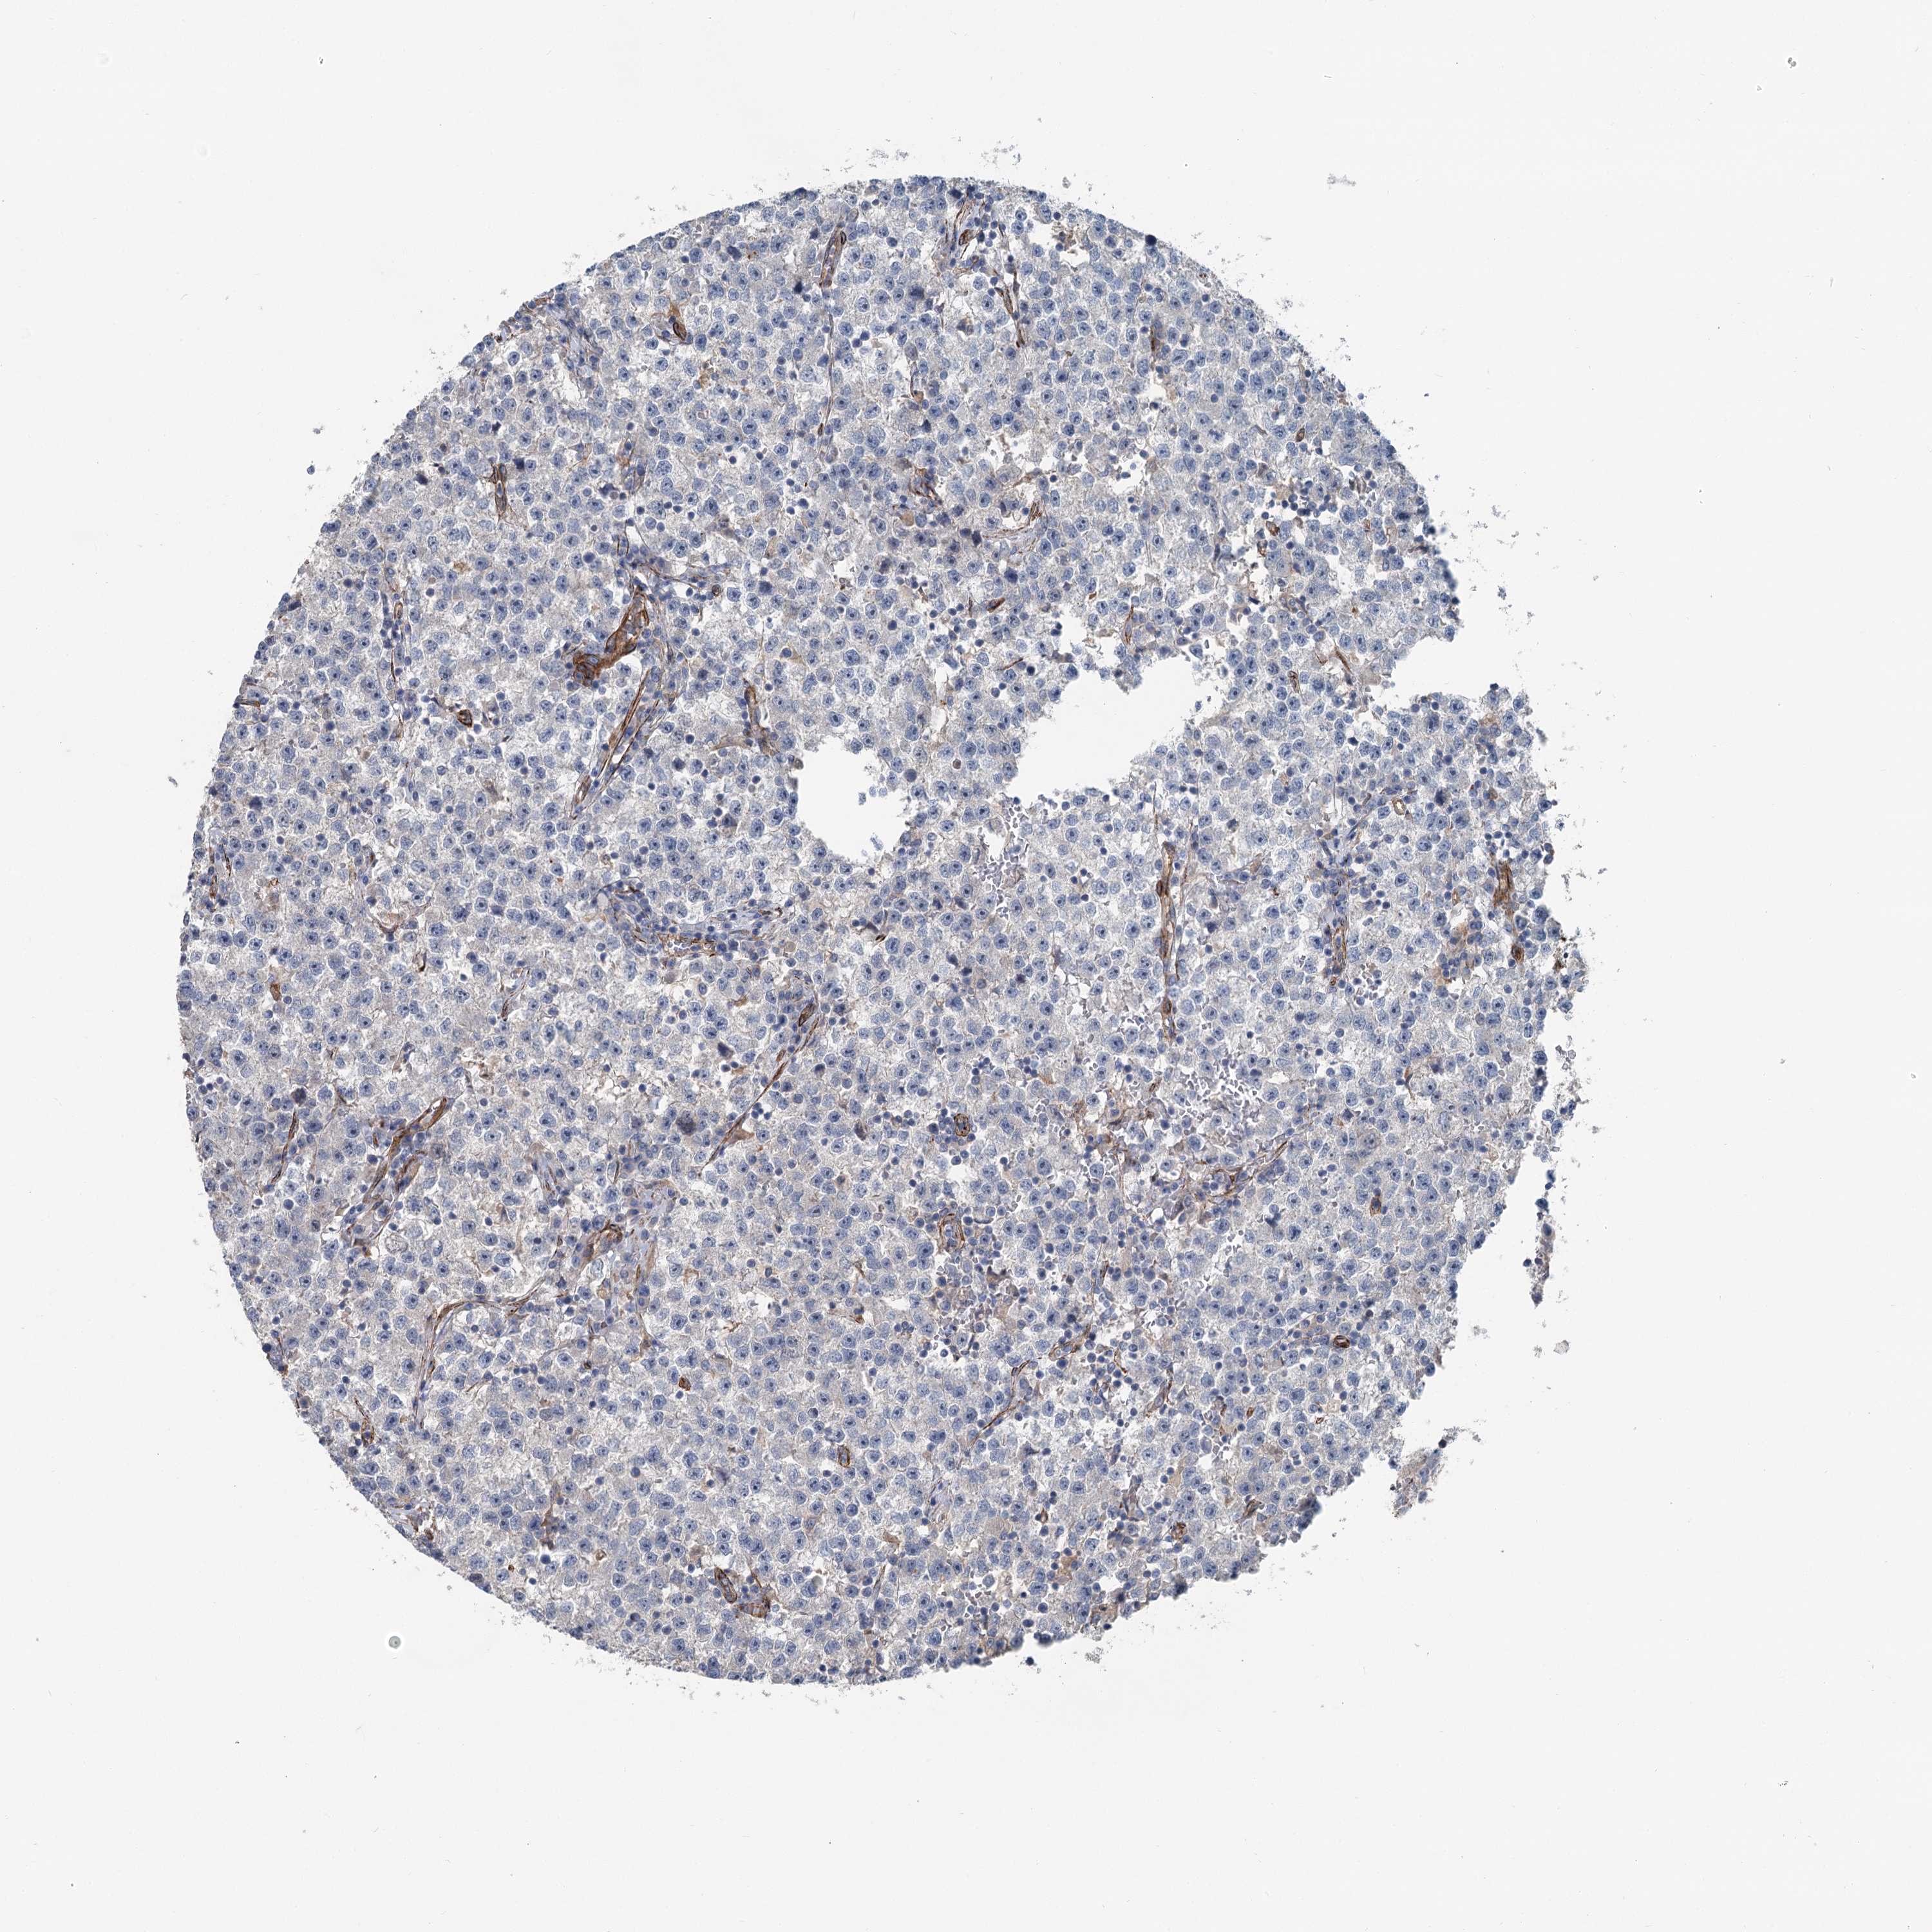

TESTIS CANCER - Protein expressioni

A mouse-over function shows sample information and annotation data. Click on an image to view it in a full screen mode. Samples can be filtered based on level of antibody staining by selecting one or several of the following categories: high, medium, low and not detected. The assay and annotation is described here.

Note that samples used for immunohistochemistry by the Human Protein Atlas do not correspond to samples in the TCGA dataset.

Antibody stainingi

Antibody staining in the annotated cell types in the current human tissue is reported as not detected, low, medium, or high, based on conventional immunohistochemistry profiling in selected tissues. This score is based on the combination of the staining intensity and fraction of stained cells.

Each image is clickable and will lead to virtual microscopy that enables deeper exploration of all samples and also displays staining intensity scores, fraction scores and subcellular localization as well as patient and tissue information for each sample.

Antibody HPA038143

Antibody HPA038144